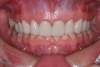

Figure 6  The full smile of case two.

Figure 6

This patient wanted to know more about improving her smile (Figure 6). She had always felt like her smile never looked quite right after she had orthodontics as a teenager. A smile with better proportion, contours, and whiter color was her goal.

The treatment-planning phase began with an examination of her current functional situation and an evaluation of signs of occlusal instability. The patient was suffering from muscular symptoms including temporal tension headaches and elevator muscle soreness and hypertrophy. Doppler auscultation, physical examination, oral history, and joint-loading testing were performed. The patient’s joints proved to be stable and in restorable condition. Examination of the teeth showed numerous signs of occlusal instability, including tooth mobility, excessive wear of the posterior teeth, and development of abfractions.

The origin of the patient’s esthetic concerns and functional issues proved to be the same: the patient was congenitally missing her lateral incisors. The solution for this esthetic deficit during her adolescent years was to move the canines into the position of the lateral incisors and then recontour (flatten the incisal edge) to make it look like a lateral. The premolars were then moved mesially into the canine position (Figure 7). The end result was a solution that closed an edentulous space, yet left a functional deficit. The premolars lacked the proper contour to allow immediate posterior disclusion in an excursive movement (Figure 8). After many years, this functional deficit led to the previously described signs of instability.